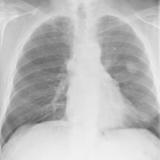

Normal Thymus